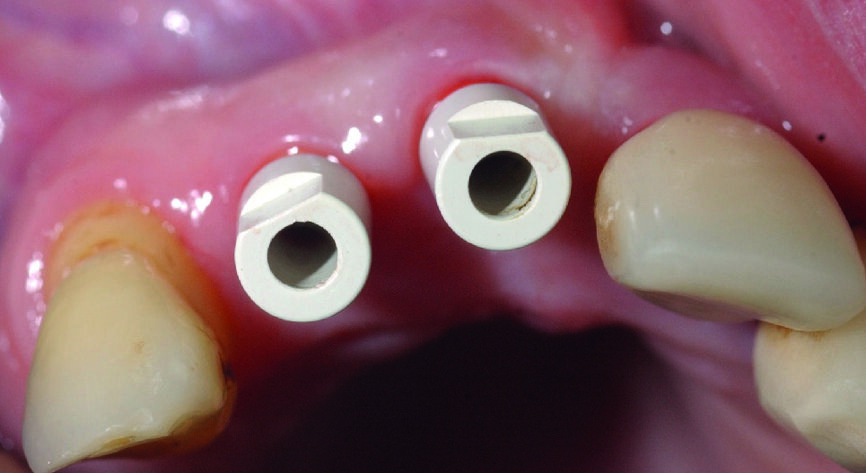

Figs. 11a & b : Vues cliniques et occlusales des scan bodies en place. Notez les positions et les axes obtenus, qui faciliteront les réalisations prothétiques définitives.

Fig. 12 : Radiographie de contrôle objectivant le bon enfoncement des scan bodies.

Des scan bodies (Core 3D), correspondant aux implants, sont positionnés et les empreintes optiques réalisées avec la camera 3Shape (Figs. 11a et b). A ce stade, il est fortement recommandé de faire une radiographie de contrôle, afin de vérifier le bon enfoncement des scan bodies et pour éviter toute erreur, qui se répercuterait au niveau de la prothèse (Fig. 12).